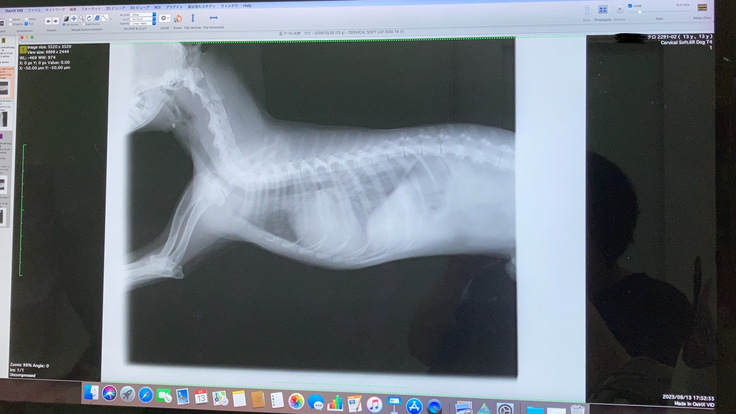

深夜救急に駆け込んだものの、病院についてのエコー・レントゲン・血液検査の結果では肺水腫の兆候は見られず…。

↑深夜救急では異常のなかった胸部が、白くなっています。